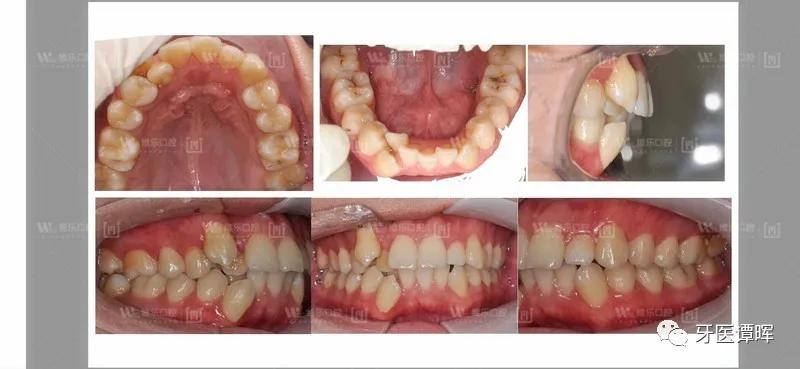

牙齿正畸前

02 检查结果

上排牙齿排列呈现拥挤,*牙虎**突出明显;下排牙齿排列错位拥挤,中线不齐,轻微深覆盖。

正畸前口内照